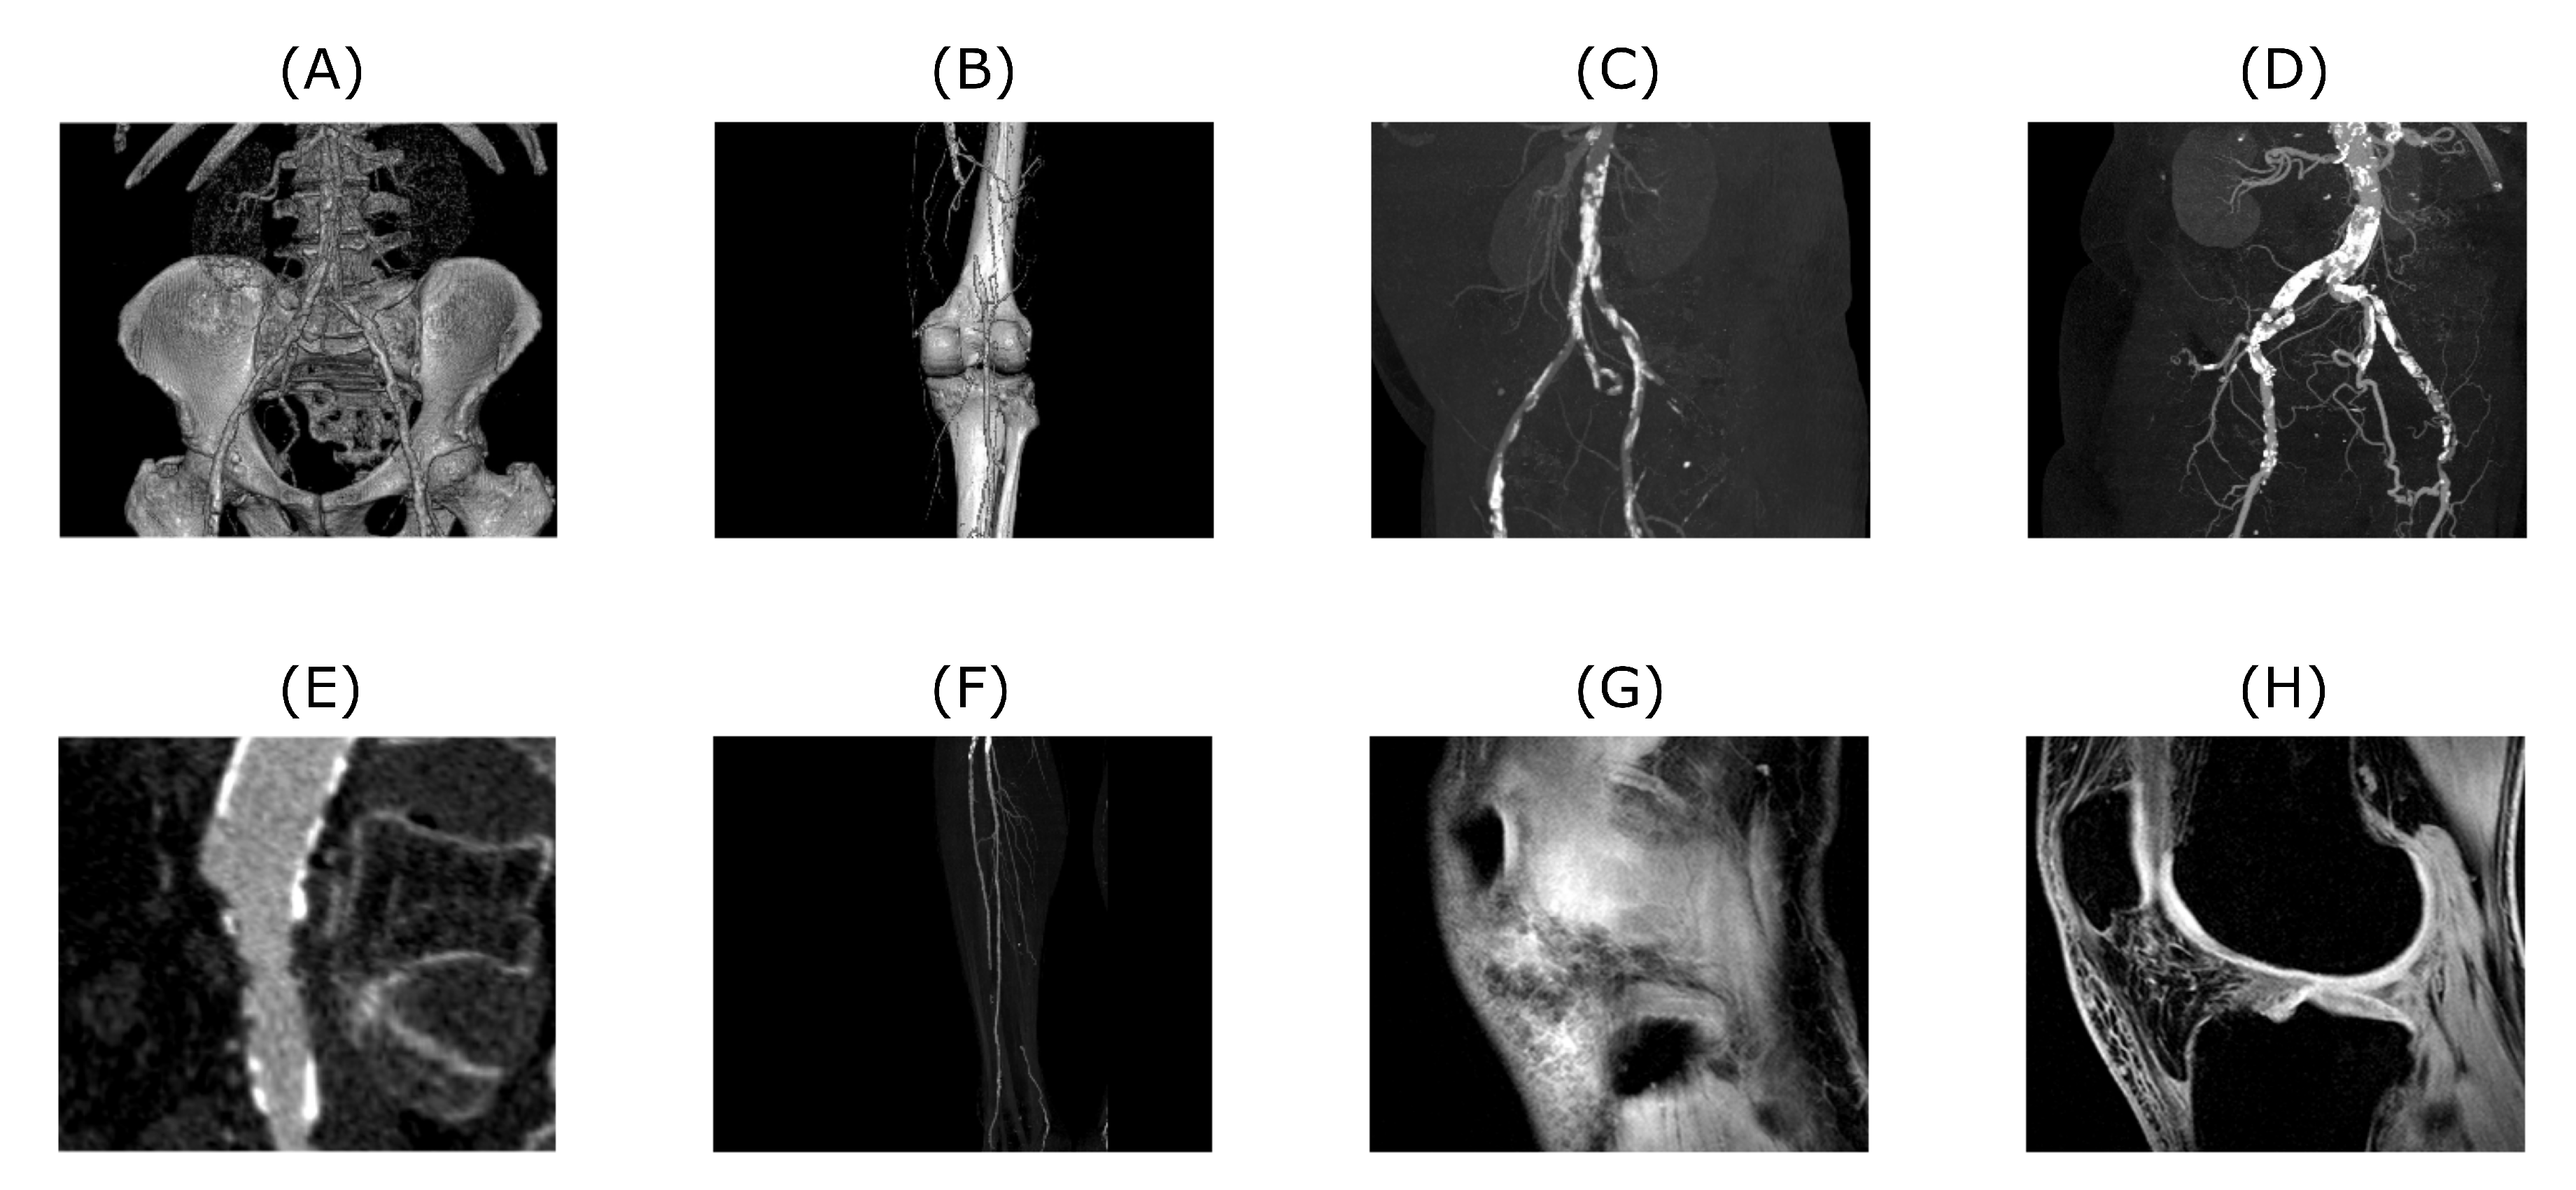

To properly analyze the performance of the approach described in the next chapter, a bank of input test data needs to be prepared and described first. In our research, we are primarily focused on the analysis of the 1D and 2D image data mostly of the musculoskeletal system. These input test data were selected to benchmark the proposed algorithm. Datasets are mostly related to the human’s musculoskeletal system, however, algorithm’s application is not limited to this specific field. As for 1D signals we used EMG measurements of hand movements from publicly available data source [56]. The algorithm’s performance of 2D datasets was tested on CT and MRI scans. CT scans are showing blood vessel calcification in the area of lower limbs. There are several levels of detail magnification so images with different properties like spatial frequency could be tested. MRI dataset is consisting of successive slices showing knee cartilage in order to test various spatial frequency images. Examples of various musculoskeletal images used for the analysis are depicted in Figure 1.

Figure 1. Examples of CT (AF) and MRI (G and H) scans used to test the proposed algorithm. Tested images are showing various level of magnification and amount of detail. Also, native noise levels contained within these images are different. Images (AF) are depicting blood vessel calcification in different details and perspectives, whereas images (GH) are showing successive slices of knee cartilage.